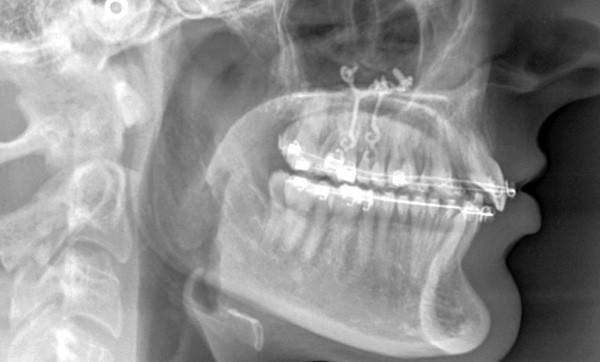

Dans un premier temps, des attaches bidimensionnelles (20/25 antérieures et 22/28 postérieures en Roth) sont collées aux deux arcades. L’alignement-nivellement est initié par des 0.014 Niti. Des plaques d’ancrages osseuses…